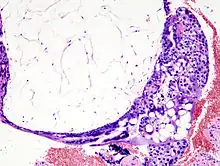

Môle hydatiforme partielle

La môle hydatiforme partielle apparaît habituellement quand un ovule est fécondé par deux spermatozoïdes. La tumeur qui en résulte est un mélange de tissu fœtal et de tissu trophoblastique anormal. S’il y a un fœtus, celui-ci est anormal.